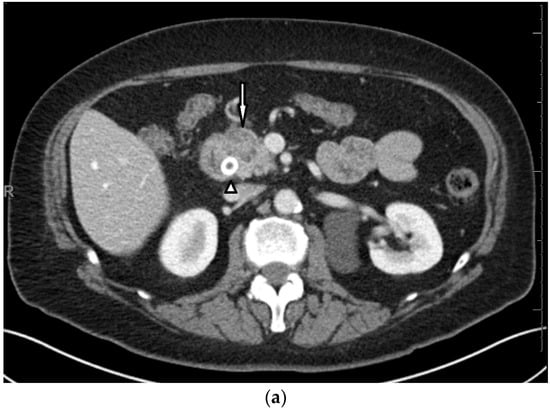

3. Case Presentation